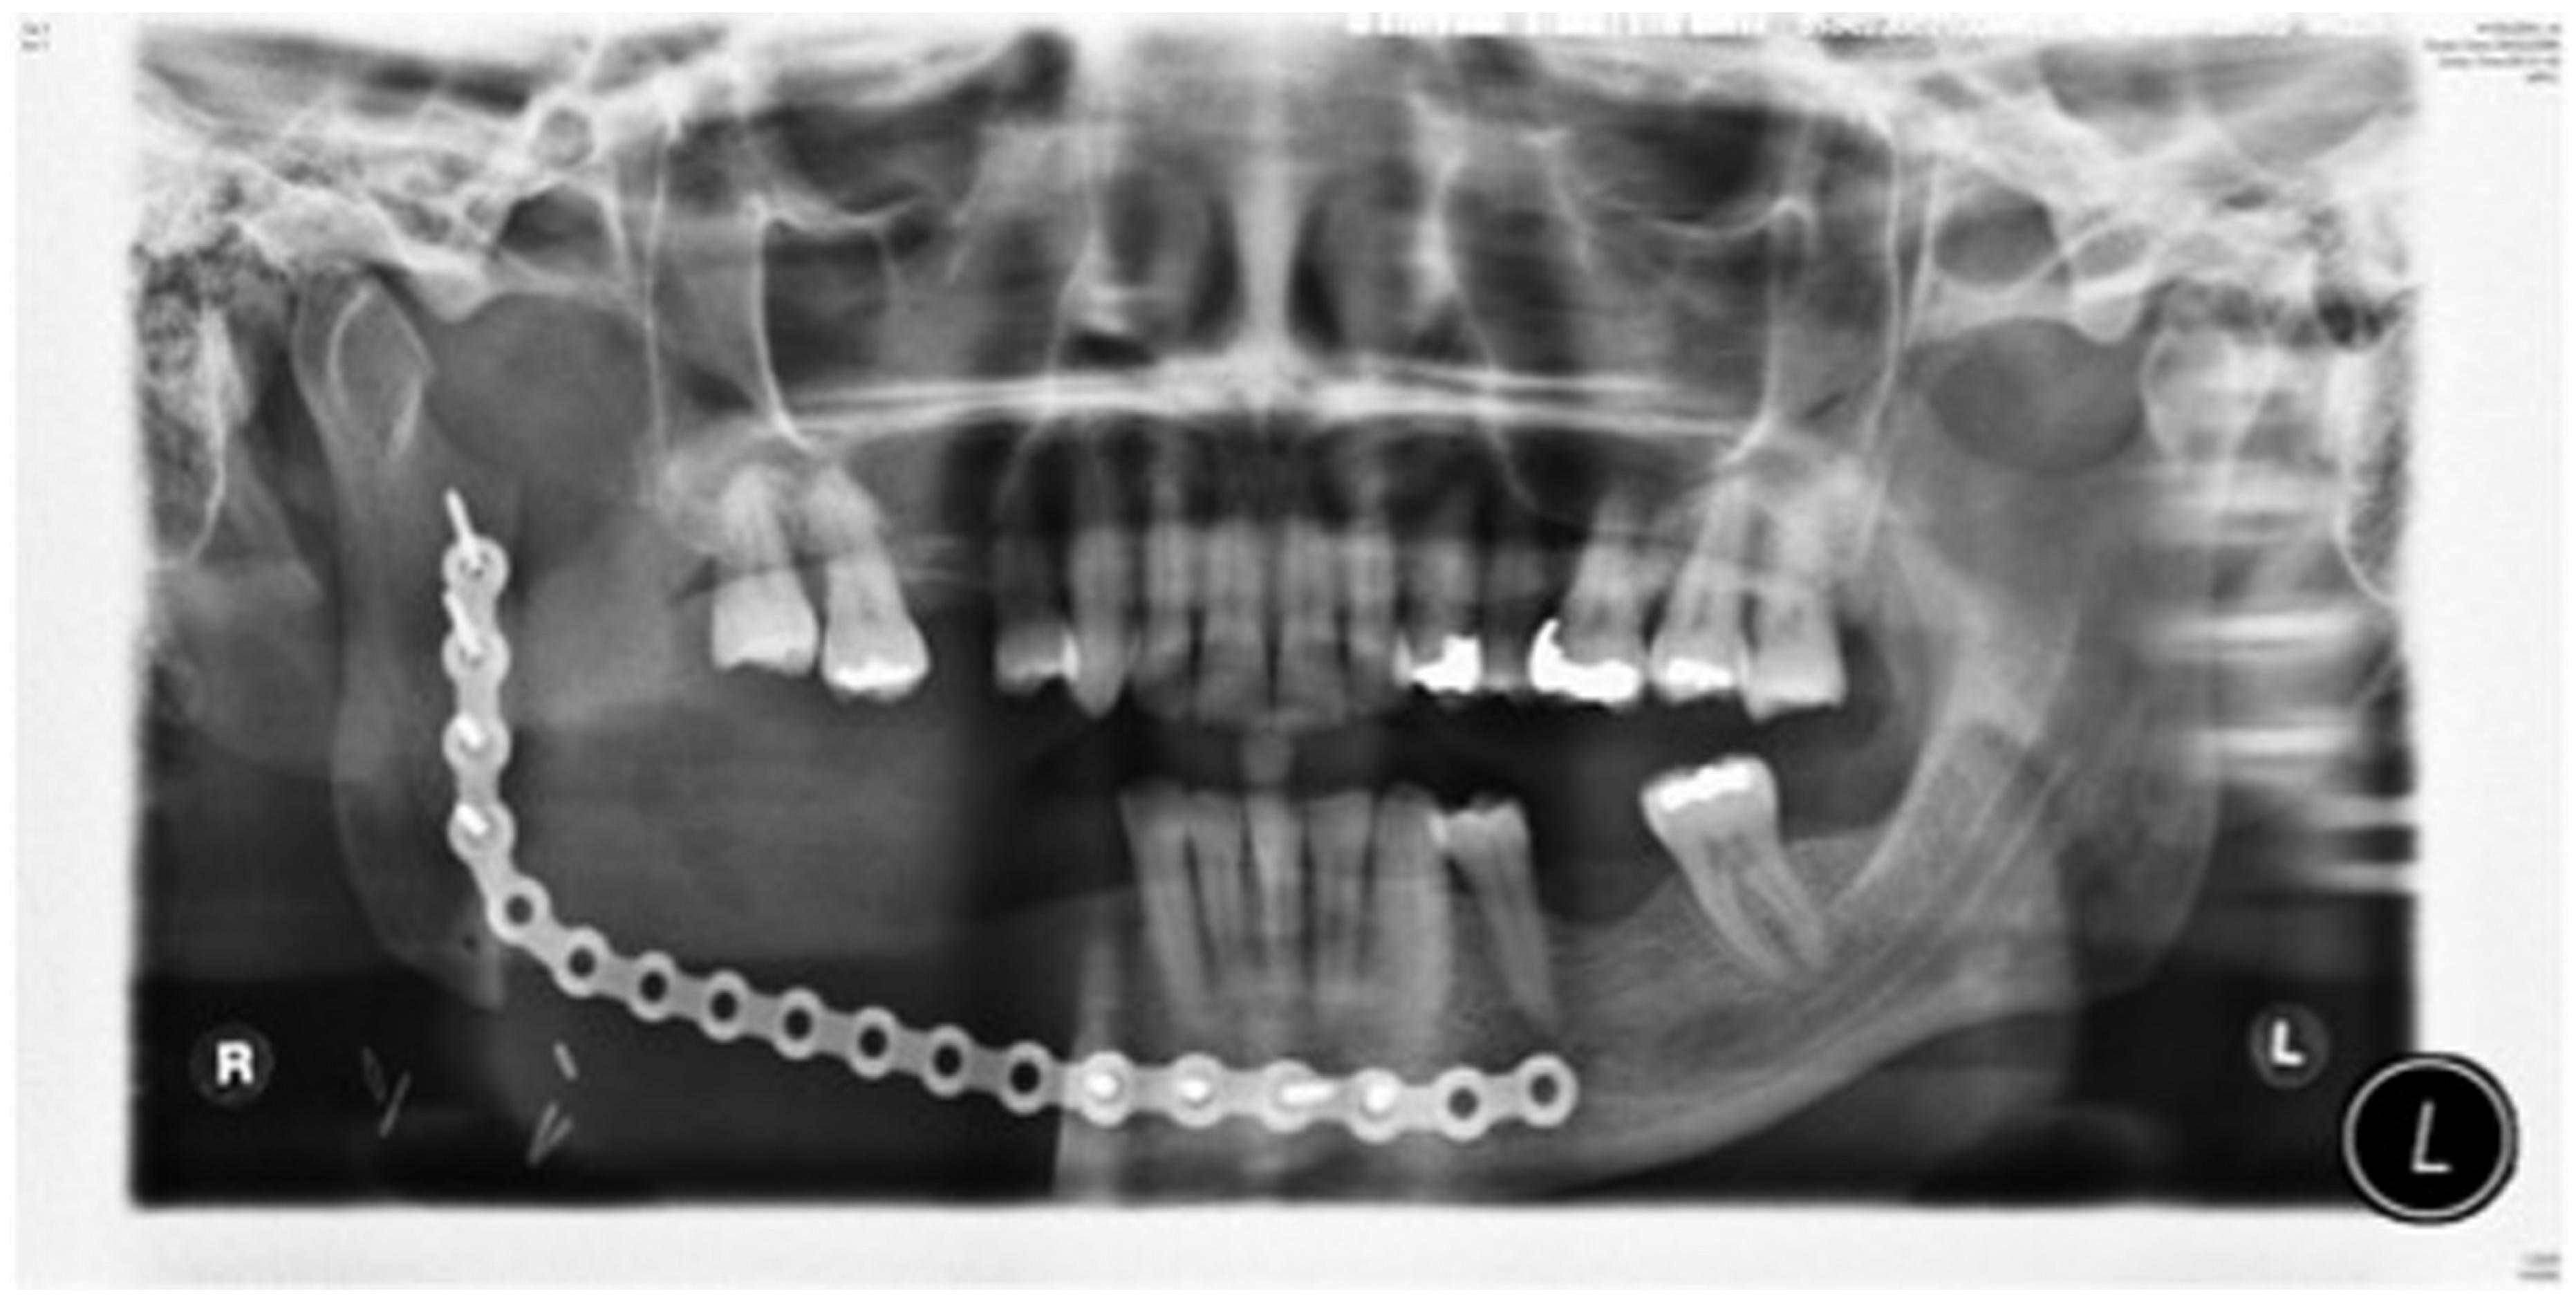

Staged reconstruction was defined as when the reconstruction with the free bone graft was performed as a secondary procedure. This secondary procedure was only performed when the oral mucosa had healed intraorally, sealing the mouth from the defect and the neck. A loadbearing locking mandibular plate was used to maintain the three-dimensional position of the bone and thus the occlusion (see Figure 1, Figure 2, Figure 3, Figure 4, Figure 5, Figure 6, Figure 7, Figure 8, Figure 9, Figure 10 and Figure 11).

Figure 3.

Locking plate to maintain the position of the bony fragments of the mandible while the oral mucosa is healing and margins of the resected pathology awaited.

Figure 10.

Stage 1 surgery. Orthopantomography (OPT) to show locking plate to maintain the position of bony fragments whilst oral mucosa is healing in gun shot wound case.

Figure 11.

Orthopantomography(OPT) showing free bone graft placed in segmental defect.